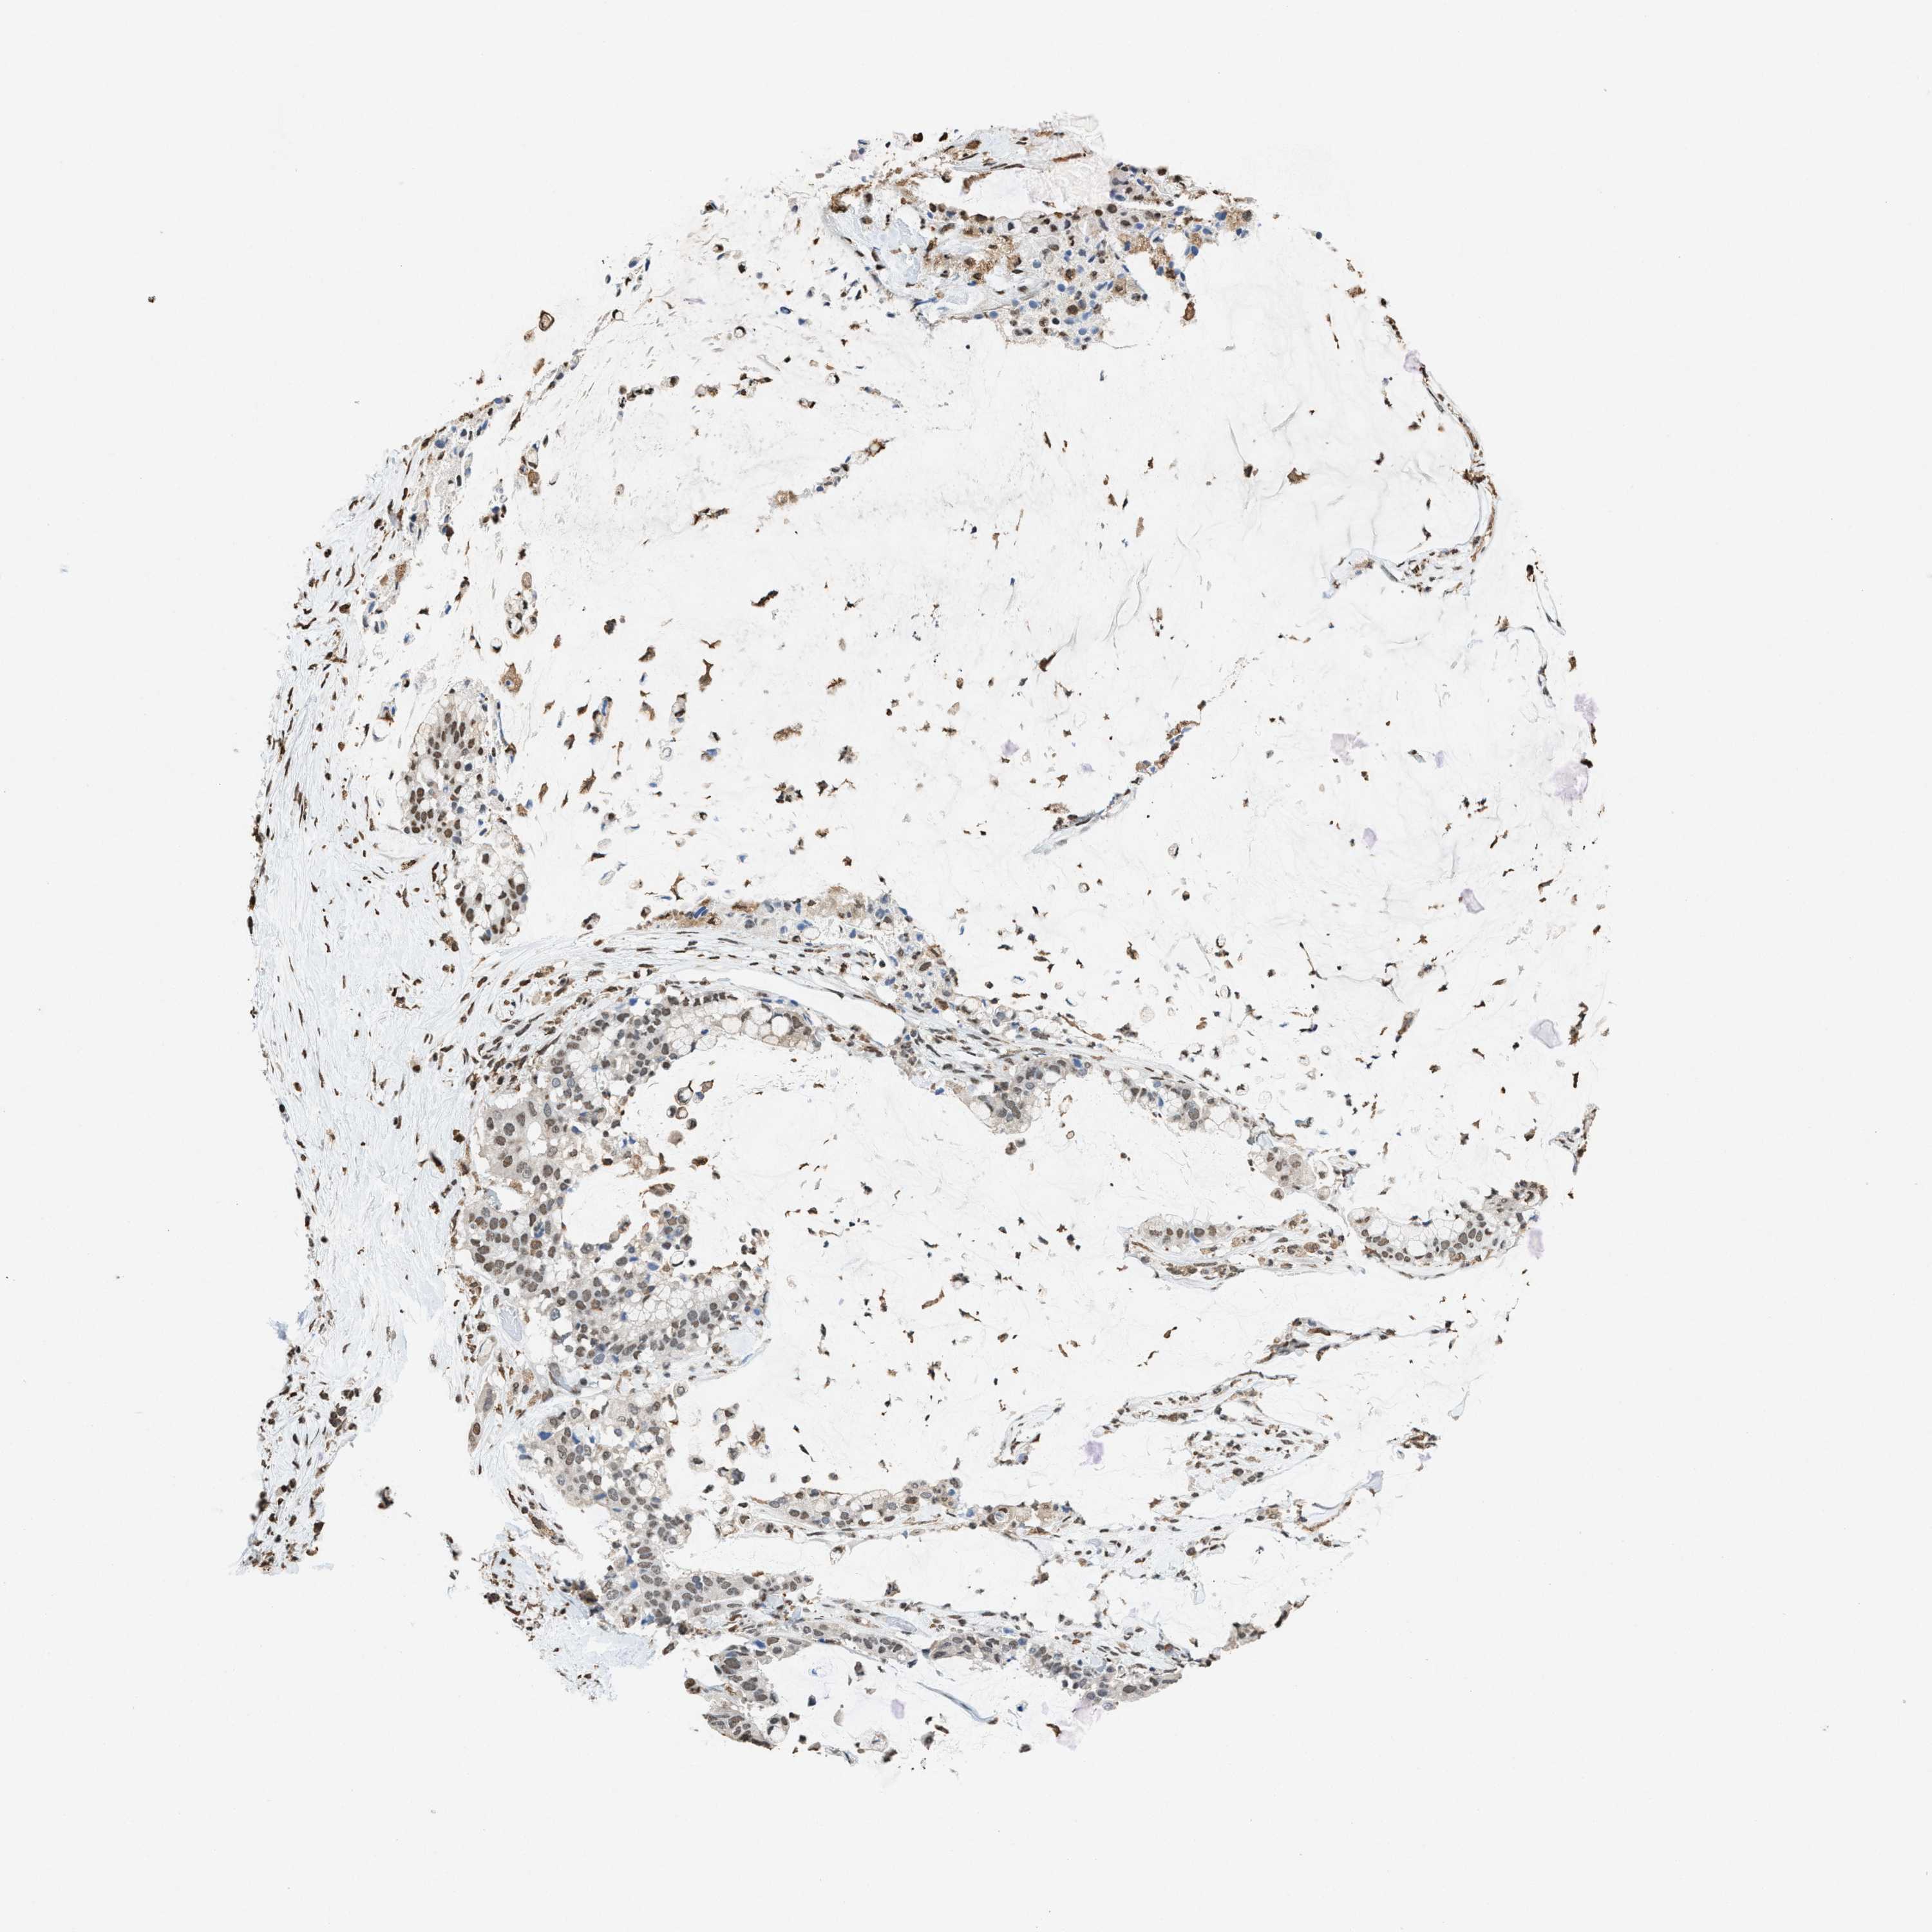

PANCREATIC CANCER - Protein expressioni

A mouse-over function shows sample information and annotation data. Click on an image to view it in a full screen mode. Samples can be filtered based on level of antibody staining by selecting one or several of the following categories: high, medium, low and not detected. The assay and annotation is described here.

Note that samples used for immunohistochemistry by the Human Protein Atlas do not correspond to samples in the TCGA dataset.

Antibody stainingi

Antibody staining in the annotated cell types in the current human tissue is reported as not detected, low, medium, or high, based on conventional immunohistochemistry profiling in selected tissues. This score is based on the combination of the staining intensity and fraction of stained cells.

Each image is clickable and will lead to virtual microscopy that enables deeper exploration of all samples and also displays staining intensity scores, fraction scores and subcellular localization as well as patient and tissue information for each sample.

Antibody HPA021816

Antibody CAB002209

Staining

High

Medium

Low

Not detected

Intensity

Strong

Moderate

Weak

Negative

Quantity

>75%

75%-25%

<25%

None

Location

Nuclear

Cytoplasmic/membranous

Cytoplasmic/membranous,nuclear

Adenocarcinoma, NOS

Adenocarcinoma, metastatic, NOS